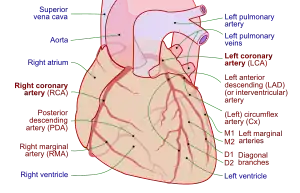

Coronary circulation

Heart tissue, like all cells in the body, needs to be supplied with oxygen, nutrients and a way of removing metabolic wastes. This is achieved by the coronary circulation, which includes arteries, veins, and lymphatic vessels. Blood flow through the coronary vessels occurs in peaks and troughs relating to the heart muscle's relaxation or contraction.[7]

Heart tissue receives blood from two arteries which arise just above the aortic valve. These are the left main coronary artery and the right coronary artery. The left main coronary artery splits shortly after leaving the aorta into two vessels, the left anterior descending and the left circumflex artery. The left anterior descending artery supplies heart tissue and the front, outer side, and septum of the left ventricle. It does this by branching into smaller arteries—diagonal and septal branches. The left circumflex supplies the back and underneath of the left ventricle. The right coronary artery supplies the right atrium, right ventricle, and lower posterior sections of the left ventricle. The right coronary artery also supplies blood to the atrioventricular node (in about 90% of people) and the sinoatrial node (in about 60% of people). The right coronary artery runs in a groove at the back of the heart and the left anterior descending artery runs in a groove at the front. There is significant variation between people in the anatomy of the arteries that supply the heart [32] The arteries divide at their furthest reaches into smaller branches that join at the edges of each arterial distribution.[7]

The coronary sinus is a large vein that drains into the right atrium, and receives most of the venous drainage of the heart. It receives blood from the great cardiac vein (receiving the left atrium and both ventricles), the posterior cardiac vein (draining the back of the left ventricle), the middle cardiac vein (draining the bottom of the left and right ventricles), and small cardiac veins.[33] The anterior cardiac veins drain the front of the right ventricle and drain directly into the right atrium.[7]